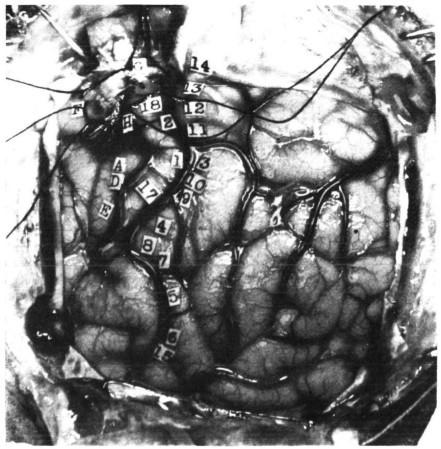

电极刺激大脑,他说左手拇指有感觉

小实:20世纪上半叶,加拿大外科医生怀尔德·潘菲尔德(Wilder Penfield)为了确定病人癫痫病灶的准确位置,在手术时用电极刺激病人大脑的各个区域。结果发现,当电极刺激大脑某个区域时,病人会说身体的某个部位有感觉。

图 2 Penfield在手术中打开、标记的病人大脑(慎点)| 图源:https://www.vox.com/science-and-health/2018/1/26/16932476/wilder-penfield-brain-surgery-epilepsy-google-doodle

小哲:不需要身体感受外界刺激,直接刺激大脑就能产生感觉?

小实:没错。